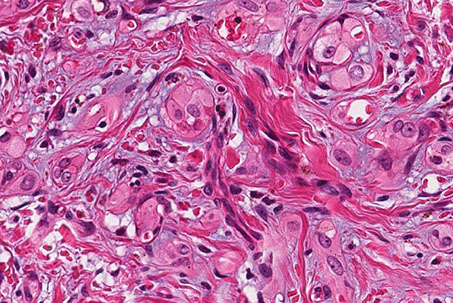

Bland-appearing angiosarcoma with multilayered endotheliom that infiltrates (splits) through collagen

Angiosarcoma can have more solid, spindly areas

C, Epithelioid angiosarcoma demonstrates focal vasoformative features. The tumor is diffusely positive for CD31 (D) and Friend leukemia integration 1 transcription factor (FLI1) (E), with a variable CD34 expression (F) (hematoxylin-eosin; original magnification x20 [D through F]).

Angiosarcoma

Rare tumor in adults, (<1% of sarcomas), ~7th decade (very rare in kiddos) derived from endothelial cells of blood vessels that can occur in multiple sites depending on type of risk factor exposure

- skin>> breast > ST > solid organs > bone

- well differentiated (hemangiosarcoma) to anaplastic tumor that can look like melanoma or carcinoma

- risk factors: chronic lymphedema, PVC, radiation (esp breast), sun exposure, Thorotrast

Micro: atypical vascular spaced lined by endothelial cells c atypia and multilayering that involves subQ and has RBCs in intracytoplasmic lumina in more solid areas

- lots of mits and necrosis

IHC: (+) Factor 8 related peptide, CD31, Ki-67, FLI-1, thrombomodulin, CD34, c-kit, VEGFR-3, ERG, INI-1 (is lost in epithelioid sarcoma)